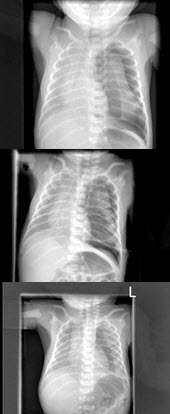

117、多项选择题

男,1岁零8个月,生长发育差,易患呼吸道感染,心悸气促,心脏正、侧位片检查如图所示,正确的描述和诊断是()

A.正位示心影向两侧扩大,心尖左移

B.肺纹理增多

C.侧位示心前间隙变窄,心后食管前三角间隙消失

D.房间隔缺损

E.室间隔缺损